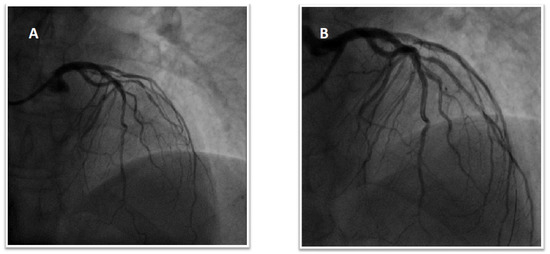

1.4. Patient 4

1.5. Patient 5